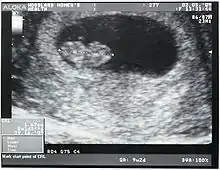

الطول التاجي المقعدي (CRL) هو قياس طول الأجنة والأجنة الحية البشرية من أعلى الرأس (التاج) وحتى أسفل الردفين (العَجُز).[1][2] ويتم تحديده عادةً من خلال التصوير بالموجات فوق الصوتية ويمكن استخدامه لتقدير العمر الحَمْلِي.

يطفو الجنين والجنين الحي في سائل سلوي داخل رحم الأم، عادةً في وضع مُقوَّس يشبه حرف C. ويمكن في الحقيقة أن يختلف القياس بعض الشيء إذا كان الجنين يُمدِّد (يفرد) جسمه بصورةٍ مؤقتة. ويتطلب القياس وجود الجنين في وضعه الطبيعي مع إبقاء جسمه غير مُمدَّد وهو وضع يشبه بالفعل حرف C. يُعَد قياس الطول التاجي المقعدي مفيدًا في تحديد العمر الحَملِي (العمر الحيضي بدايةً من اليوم الأول لآخر دورة شهرية)، وهكذا، يتحدد تاريخ الولادة (EDD). وينمو أطفال مختلفون بمعدلاتٍ مختلفة، ومن ثمَّ، يُعتبر العمر الحملي مسألة تقريبية. وأشارت الأدلة الحديثة إلى أن نمو الطول التاجي المقعدي (وبالتالي التقدير التقريبي للعمر الحملي) قد يتأثر بعوامل تتعلق بالأم، مثل: العمر، وتدخين، وامتصاص حمض الفوليك. في بداية الحَمْل، يكون دقيقًا خلال -/+ أربعة أيام، ولكن تقل نسبة الدقة لاحقًا أثناء الحمل بسبب اختلاف معدلات النمو. في هذه الحالة، يمكن اللجوء إلى عوامل أخرى بجانب الطول التاجي المقعدي. أما طول الحبل السري، فيتساوى تقريبًا مع الطول التاجي المقعدي أثناء الحمل.